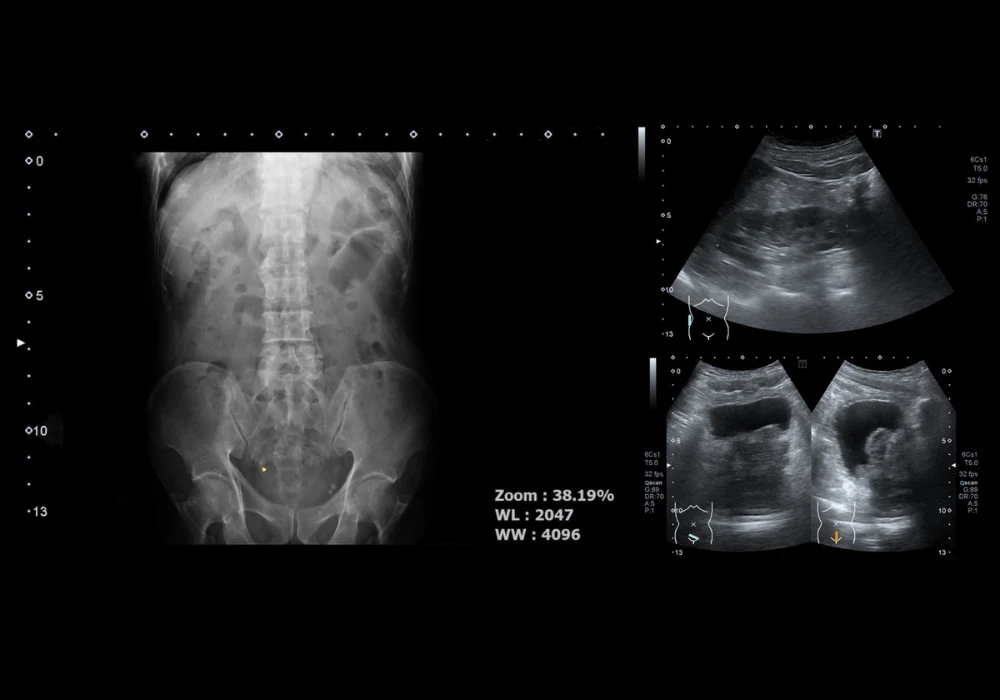

The development of SRUI relies on algorithmic processing of CEUS video data to track microbubble contrast agents, effectively reconstructing vascular architecture at a microscopic level. Initially, tracking algorithms underwent validation using synthetic in silico data, followed by preclinical trials involving CEUS imaging of sheep ovarian tissue, which provided a dense microvascular structure analogous to tumour environments. The transition to human prostate imaging involved retrospective analysis of CEUS data from 14 patients, where 54 imaging planes were examined and suspected cancer regions were identified through biopsy correlation.

Super-resolution imaging revealed notable vascular differences between malignant and benign prostate tissue. Among the 10 imaging planes with confirmed Gleason 7 cancer, seven exhibited high-flow and high-volume vascular regions, while six demonstrated a combination of avascularity and increased blood flow. These distinct microvascular patterns suggest that SRUI can provide essential biomarkers for prostate cancer localisation.

One significant case study (P127) illustrated highly angiogenic cancer, where biopsy-confirmed cancer regions corresponded with areas of increased vascular density and velocity. Conversely, another case (P134) presented a nonangiogenic tumour with an avascular region surrounded by higher-flow areas, suggesting possible ischaemic or hypoxic tumour conditions. These findings highlight the variability in vascular presentations of prostate cancer and reinforce the need for further investigation into multiparametric SRUI biomarkers.